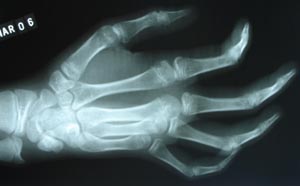

Rheumatoid Arthitis

Rheumatoid arthritis is polyarthritis due to inflammatory overgrowth of the synovium. Earliest change is perarticular soft tissue swelling & osteoporosis. It involves hands & feet mainly metacarpo & metatarsophalangeal joints.